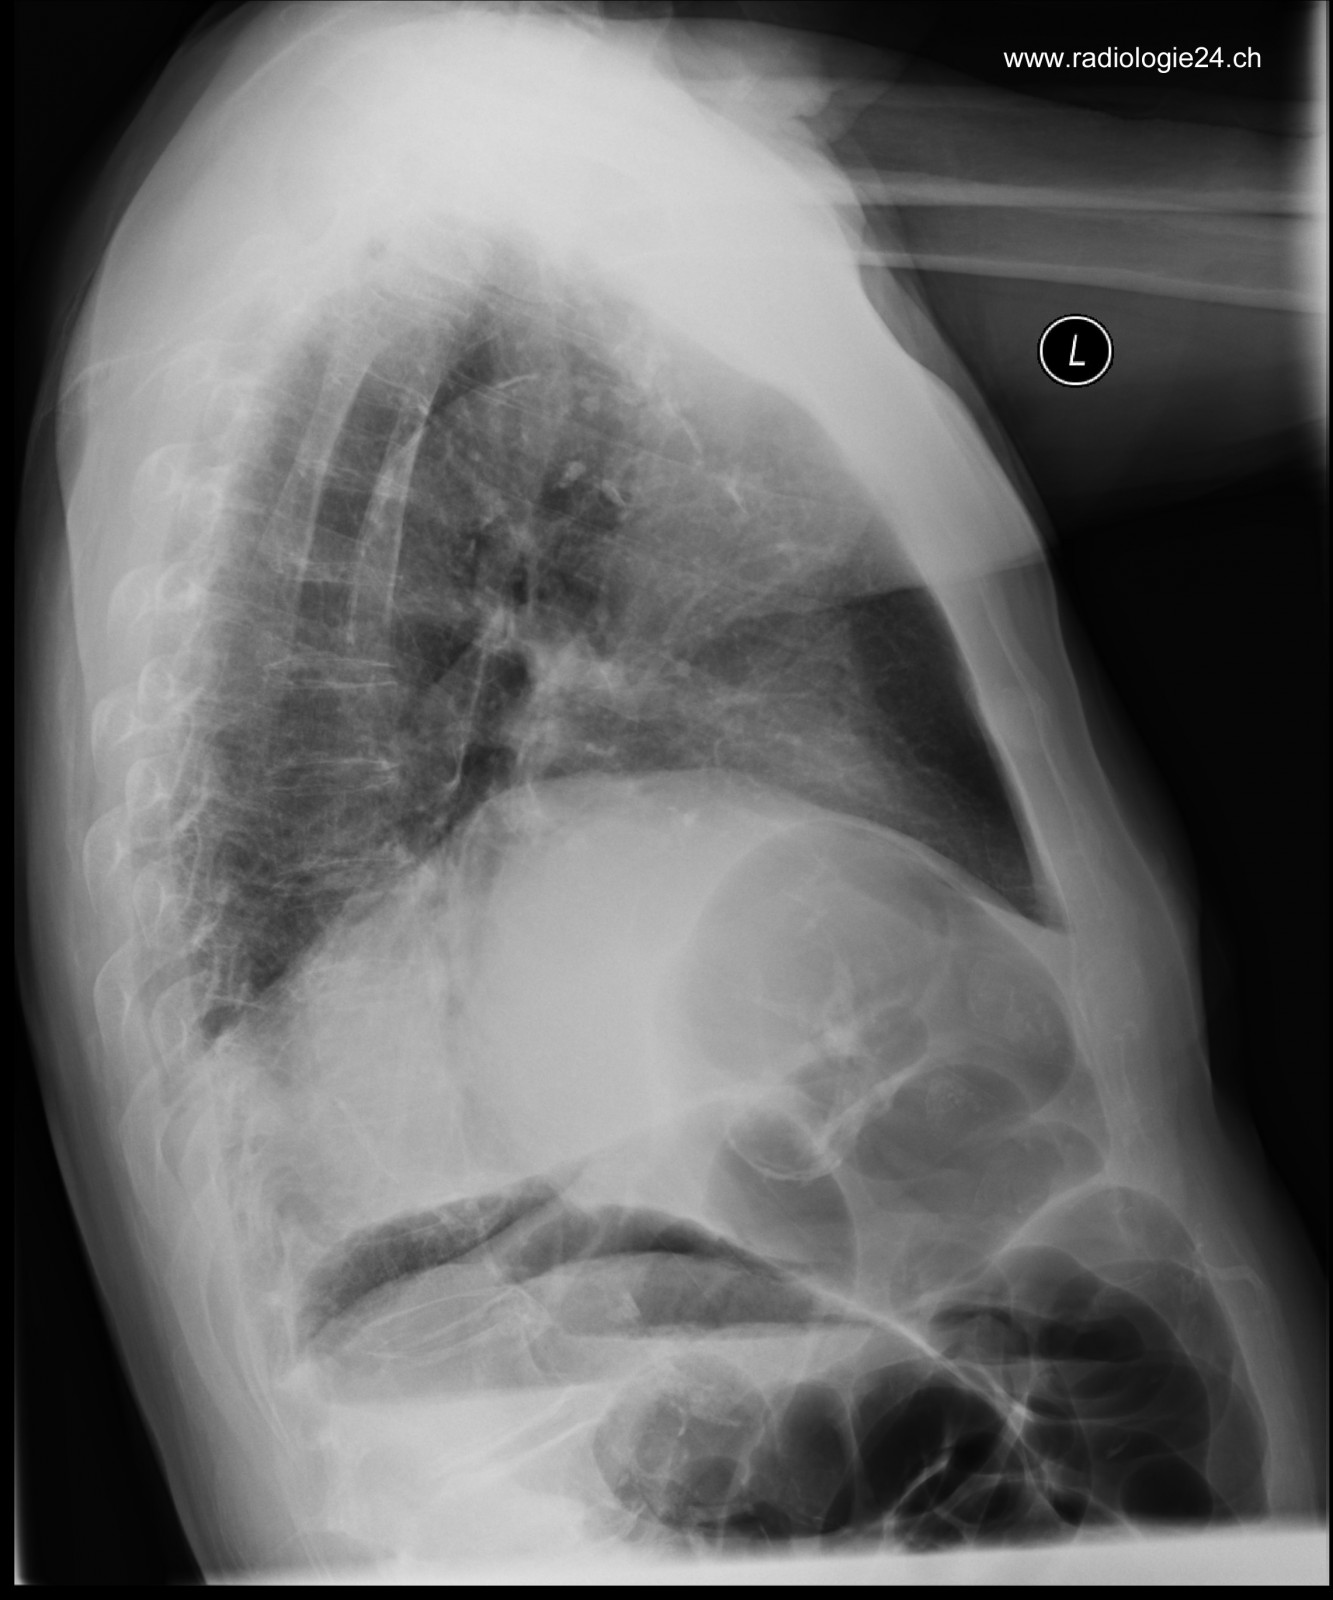

Röntgenfall des Monats Juli 2017 mit Auflösung

78 jähriger Patient mit zunehmender Dyspnoe und Thoraxschmerzen

seitlich